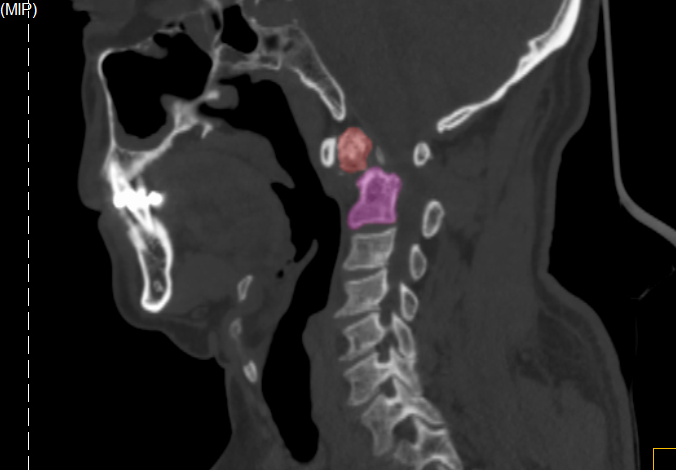

王先生術(shù)前CT

王先生術(shù)后CT

8月23日,手術(shù)團(tuán)隊(duì)為王先生進(jìn)行頸后入路寰樞椎復(fù)位內(nèi)固定術(shù)+頸椎植骨術(shù),2小時(shí)手術(shù)順利完成。術(shù)后,上頸椎齒狀突陳舊性骨折順利復(fù)位,王先生雙上肢酸痛、麻木感基本消失,步態(tài)不穩(wěn)得到明顯改善,困擾了他30余年的疼痛也隨即消失。9月6日,患者康復(fù)出院。